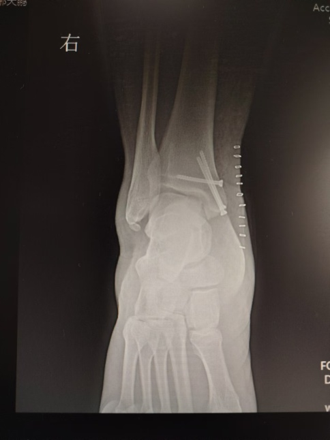

李恒和李亚峰共同上台,先在内踝处做长约4cm的切口,显露内踝骨质,再用3枚2.0mm克氏针先进行截骨平面和固定螺钉位置定位,“C”臂透视,克氏针位置合理

骨刀做内踝“V”形截骨,显露距骨骨软骨损伤部位,环形取骨器取出坏死囊变组织

环形取骨器取出等大的骨软骨柱移植到距骨,3枚螺钉固定截骨内踝